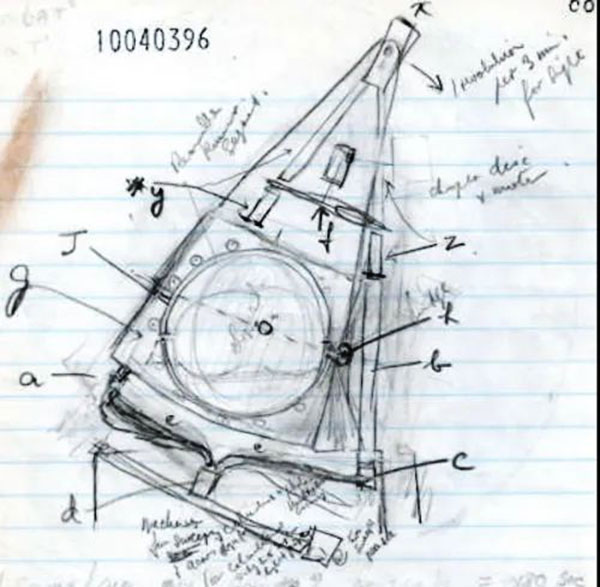

Хаунсфилд сформулировал новый подход к проблеме визуализации того, что находится внутри черепа. Сначала он разделил мозг на воображаемые слои. Затем планировал провести серию рентгеновских лучей через все эти слои, повторяя это для каждого градуса полукруга. Один луч при этом будет пойман детекторами на противоположной стороне.

Интересно отметить, что Хаунсфилд признал устройство Ольдендорфа, запатентованное в США в октябре 1963 года, как единственную другую попытку томографической реконструкции. Годфри задался вопросом, сможет ли система теоретически распознать текст в закрытой книге, освещая каждую страницу под разными углами и измеряя выходящий сигнал. Хаунсфилд предположил, что при достаточном количестве информации можно определить, что написано на странице.

Его идея заключалась в создании машины, способной генерировать трёхмерные изображения мозга. Устройство должно было проецировать узкие пучки рентгеновских лучей через голову человека, а компьютер — использовать полученные данные для создания серии поперечных сечений, которые вместе представляли бы мозг в 3D-формате.

Совместно с коллегой Стивеном БЕЙТСОМ из CRL он усовершенствовал свою концепцию, используя простейшую арифметику, доступную на тот момент. Его идеи были во многом схожи с идеями Аллана Кормака, но Хаунсфилд смог разработать более совершенную математическую модель, хотя и не был знаком с предыдущими математическими подходами в этой области.